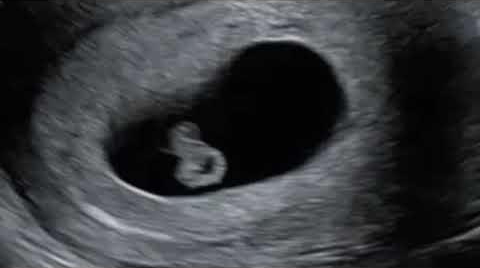

Bebeğin görüntüleri: